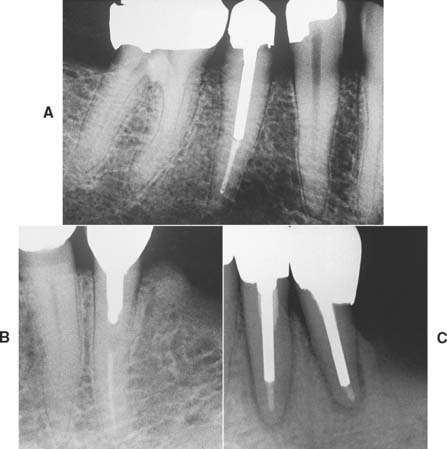

If the coronal structures are largely intact and loading is favorable, as on anterior teeth that are farther removed from the fulcrum (see Chapter 4), a simple filling can be placed in the access cavity (Fig. 12-2A). However, if a substantial amount of coronal structure is missing, a cast post and core is indicated instead (Fig. 12-2B). Molars are often restored with amalgam or a combination of one or more cemented posts and amalgam or composite resin (Fig. 12-2C and D).

Fig. 12-2 A, An anterior tooth with an intact clinical crown can be predictably restored with a composite restoration in the access cavity. B, When most coronal tissue is missing, a cast post and core is indicated to obtain optimal tooth preparation form. C, In mandibular molars, an amalgam foundation is retained by a cemented prefabricated post in the distal canal. D, In maxillary molars, the palatal canal is most often used.